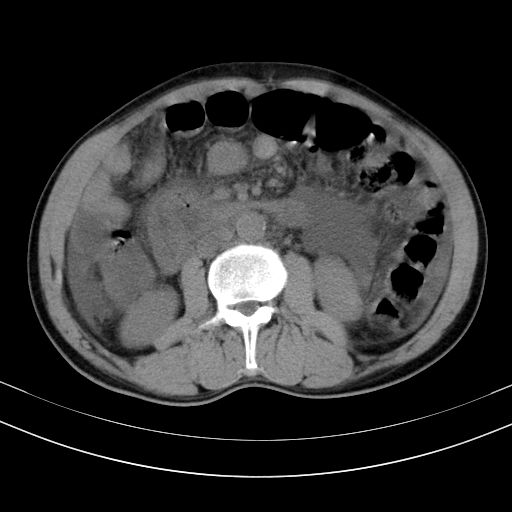

以下是引用随光逐影在2010-2-28 10:23:00的发言:[br]1)考虑肝癌;建议行ct增强扫描检查。2)肝硬化,脾大,腹水。3)慢性胆囊炎。

以下是引用dyqct在2010-2-28 16:44:00的发言:[br][quote]以下是引用随光逐影在2010-2-28 10:23:00的发言:[br]1)考虑肝癌;建议行ct增强扫描检查。2)肝硬化,脾大,腹水。3)慢性胆囊炎。